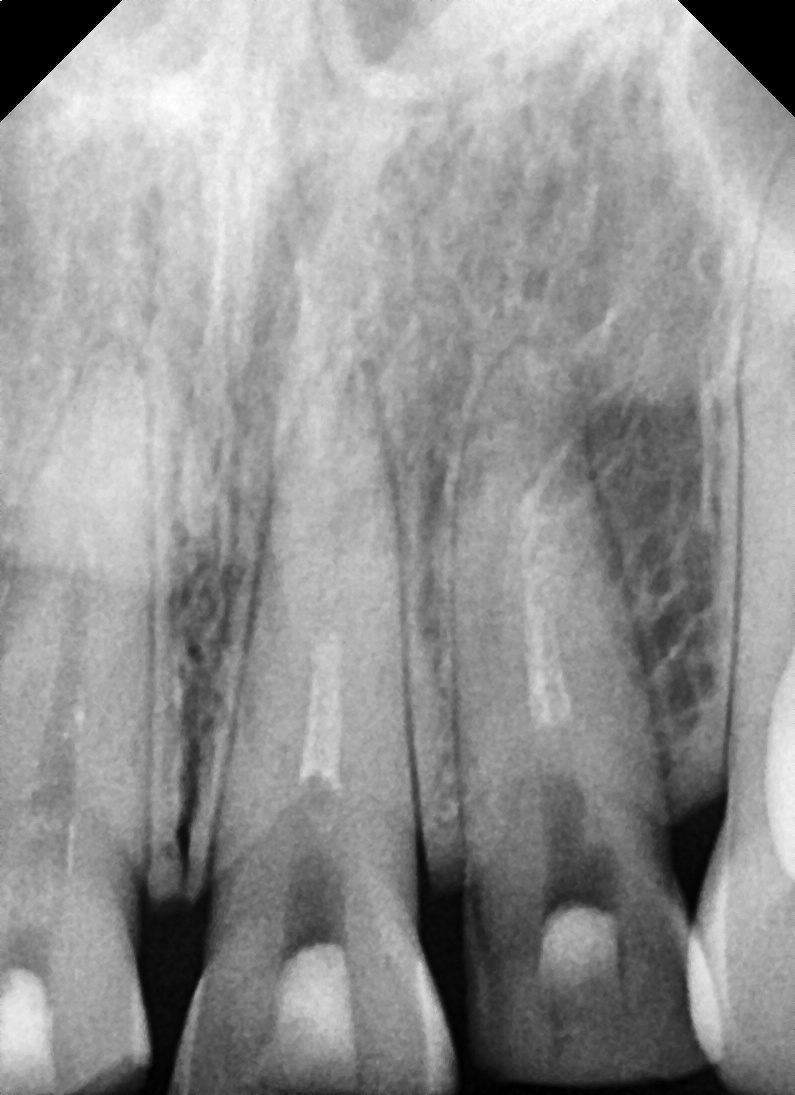

Diagnostic results

Fractures were confirmed in four maxillary front teeth.

Some teeth had exposed pulp and required root canal treatment,

and due to severe discoloration and fracture, we determined that

a crown restoration would be more appropriate than a simple resin restoration.

① Root canal treatment

– Removed inflammation and damaged pulp inside the tooth,

and prevented infection through root canal therapy.